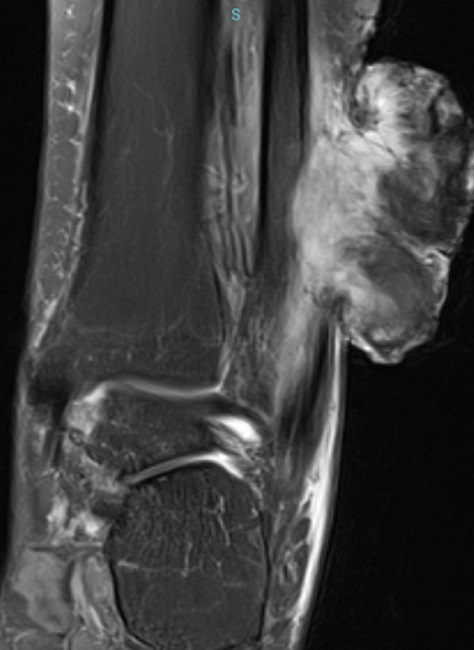

Os exames bioquímicos gerais foram normais, porém, à ressonância nuclear magnética, foi evidenciada a invasão da fíbula distal (Figura 7).

O conjunto de achados histopatológicos, imunofenotípicos e de imagem são diagnósticos de histiocitoma fibroso maligno (profundo)/sarcoma pleomórfico indiferenciado, estágio IIIA.

Ressonância magnética é a modalidade de imagem de escolha para avaliação de sarcomas de tecidos moles, especialmente para determinar a extensão local da lesão. Ao exame, o MFH mostra um padrão heterogêneo hiperdenso em imagens ponderadas em T2 e isodenso aos músculos em imagens ponderadas em T1.19